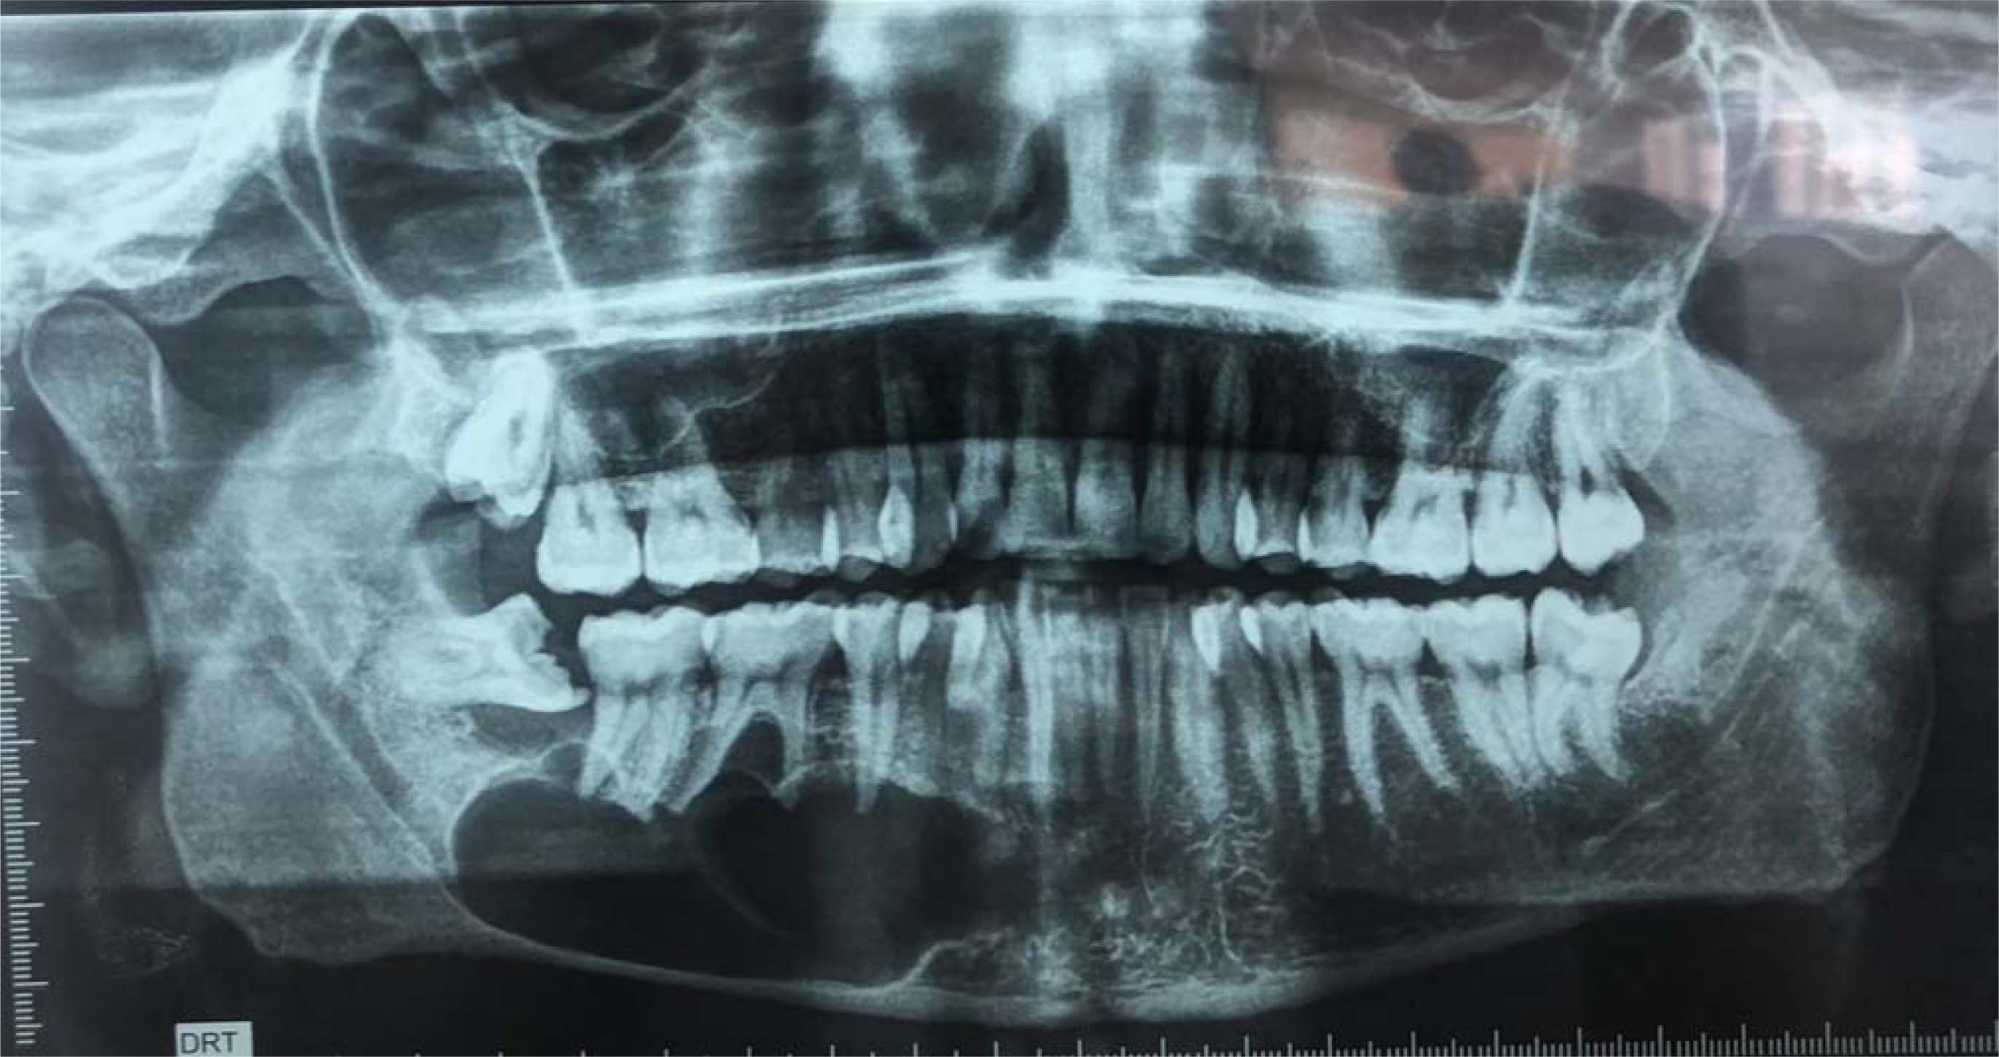

A 28-year-old male patient, a non-smoker in good general health, was referred to the Department of Surgical Odontology with complaints of persistent numbness in the right lower lip and chin following the surgical extraction of the right mandibular third molar. The patient reported no improvement in symptoms 10 days after the procedure. Clinically, he presented with complete numbness and loss of sensation affecting the right half of both the lower lip and the chin. A panoramic radiograph revealed close proximity between the extraction site and the inferior alveolar nerve (IAN) (Figure 1).

Figure 1. Panoramic radiograph: contact of the site of the right mandibular tooth with IAN.